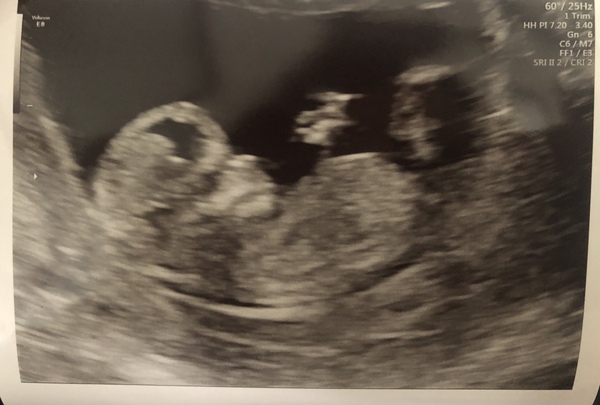

Aimy1 · 15/07/2020 16:32

Got a great scan picture today. Took 3 attempts to try and get the baby to keep still including emptying my bladder and having a 15 min walk. Alls good. I am now undecided on my maternity leave. I am think of leaving at 29 weeks. So I can spend as much time witb my other children as I can and to have some me time to prepare and to minimise the chance of me getting pnd again. I've also got to have growth scans after 30 weeks because my daughter was slightly small. So leaving work early means I don't have to keep booking time off which my boss wouldn't like as working in a childminders, its hard to get cover.

Skyla01 · 16/07/2020 08:16

@Aimy1 lovely photo, glad everything is well with your scan! Your plan sounds sensible, and it helps you have experience to guide you. I was thinking of stopping at 36 weeks, my last week or two could be over Xmas holidays so would only be in a few days, not the whole week. I'll try and save up a bit of annual leave too. However never been pregnant before so will just have to see how it goes! I'm hoping to have saved some more money by then so if I want to take mat leave earlier I don't need to worry so much about money.

Aimy1 · 22/07/2020 08:48

@OrangeJ guessing the sex, i would say boy. When we found out we were having a girl, she showed us 3 little white lines where privates are and that means girl and boy is a nub. I cant see 3 lines there and sure I can see a little nub but that could be something completely different πŸ˜‚.

Aimy1 · 22/07/2020 08:50

This is my daughters scan. Not sure if you can see the 3 lines.